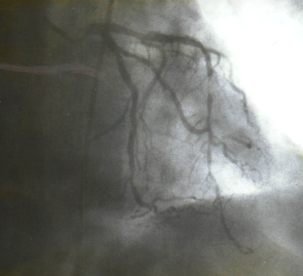

Первичный отбор больных ИБС, рефрактерных к медикаментозной терапии, на операцию ТМЛР осуществлялся по данным коронарографии. Основанием для отбора больных на ТМЛР явилась идентификация множественного поражения коронарных артерий в виде “четок” (рис. 3), диффузного поражения КА с выраженным сужением просвета, либо с полным его закрытием, когда просвет сосуда представлен непроходимыми тяжами, перемежающимися с ”островками” бывшего коронарного русла, заполненного контрастным веществом через коллатерали (рис 4).

Рис. 4. Коронарограмма больного Б., 42 лет. Боковая проекция (LAO 900). «Островки» бывшего коронарного русла ПМЖВ